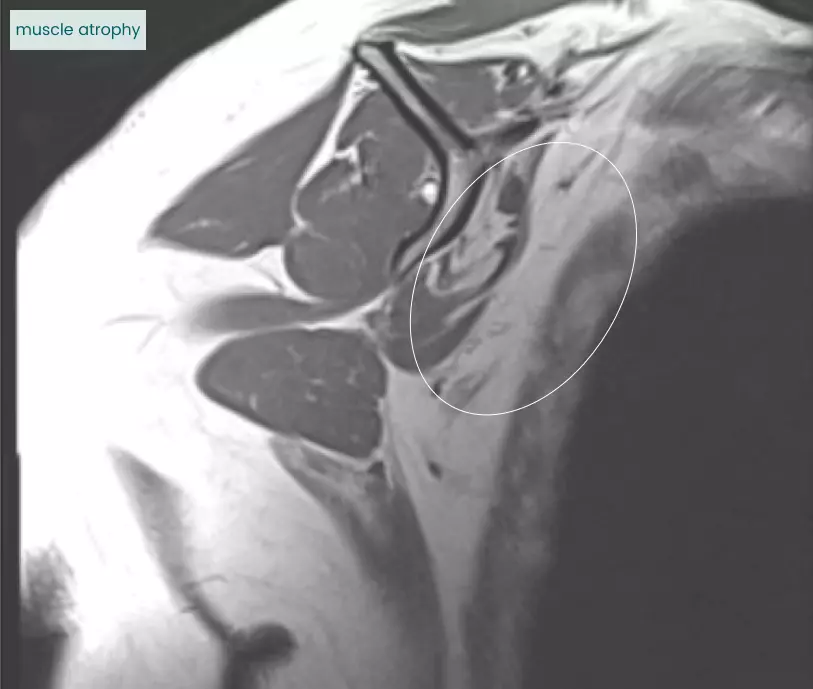

Errors in interpretation can send patients down the wrong treatment path.

Failure to describe the muscle atrophy accompanying this rotator cuff tear represents a missed chance to flag that the patient may be a poor candidate for surgery and unlikely to recover well.

Atrophied

Normal